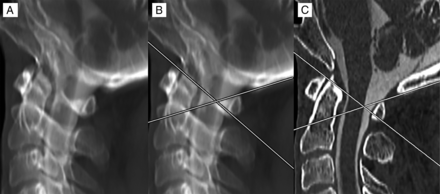

The relative location of the C1 posterior arch triangular FP to the dorsal spinal cord border was determined in all cases by the following methods: 1) A maximum-intensity-projection image was generated for each cervical myelogram using sagittal reformats of high-resolution (1-mm-thick) axial images. An MIP thickness of 3.5 cm was used to simulate the appearance of the C1 arch projecting over the spinal canal on a lateral fluoroscopic view, with alignment adjustments performed to ensure that the bilateral posterior arches precisely overlapped. 2) Two lines were drawn to approximate the angle of the anterolateral and posterior arches—the first line tangential to the superior cortex of the anterolateral arch and the second line tangential to the superior cortex of the posterior arch. 3) The FP apex was determined at the point where these lines intersected. 4) The distance of the FP apex to the dorsal margin of the spinal cord was measured. If this line was anterior to the cord, negative measurement values were used, and if the line was posterior to the cord, positive measurement values were used (Fig 2). Measurements were performed by a neuroradiology fellow and neuroradiology attending physician.

Method of measurement for the C1 posterior arch FP. An MIP image was created of a high-resolution sagittal reformatted cervical CT myelogram. Alignment adjustments were performed to overlap the bilateral posterior arches (A). Lines were drawn tangential to the superior cortex of the anterolateral and posterior arches. Where these lines overlapped was considered the FP (B). The MIP was then converted back to a 1-mm-thick section to evaluate the position of the FP from the dorsal spinal cord, which, in this case, showed direct correspondence, measuring 0 mm (C).